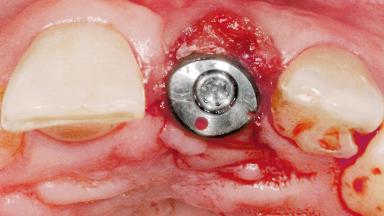

Type of Implants One-Piece

Attachment One-Piece

Placement Protocol Early or late implant placement